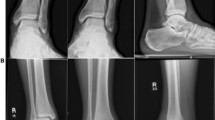

The classical fixation of syndesmosis ruptures accompanied by a malleolar fracture is a single 3.5 mm cortical screw positioned between 1 and 4 cm above the ankle joint level (Fig. 7) after fixation of the distal fibula [41, 125]. The screw is not over drilled to avoid lagging. The anterior tibiofibular ligament is sutured separately or reattached with a small or mini-fragment screw in cases of bony avulsion at the distal tibia or fibula. In cases of pure ligamentous syndesmosis rupture––including Maisonneuve injuries, in the authors’ practice a second screw is introduced parallel to and above the first one to assure rotational stability [90]. The two screws can be connected by a small two-hole plate to increase torque resistance, e.g., in osteoporotic bone [33].

a, b In ankle fracture-dislocations with syndesmotic disruption, internal fixation of the distal fibula and medial malleolus is followed by transsyndesmotic screw fixation (same patient as in Fig. 4). c, d At 1 year follow-up and complete implant removal at the ankle, the mortise is stable without signs of posttraumatic arthritis. Salvage of the ankle joint was particularly important in this case because the subtalar joint had to be fused after a comminuted calcaneal fracture